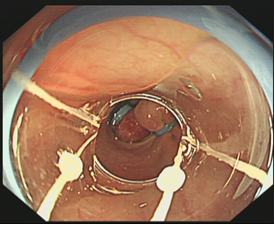

肝病科請消化內(nèi)科主任張曼曼會診后,經(jīng)過與趙健雄主任討論并聯(lián)合組建ICU(大營路)、麻醉科MDT救治團(tuán)隊(duì),在分析患者上消化道出血原因后,建議立即行內(nèi)鏡下止血。專家團(tuán)隊(duì)就術(shù)中可能出現(xiàn)的出血導(dǎo)致視野不清、破口難以發(fā)現(xiàn)、血壓持續(xù)下降等情況進(jìn)行了充分模擬討論并制定了應(yīng)對方案。在與患者家屬進(jìn)行溝通后立即行急診胃鏡下套扎止血,術(shù)中可見食管曲張靜脈活動性噴血,患者靜脈曲張最粗直徑約1.2cm,確定出血點(diǎn)后,在內(nèi)鏡室主管護(hù)師方婷默契配合下安裝套扎器,李佳醫(yī)師對出血點(diǎn)行套扎止血治療,隨后于其它曲張靜脈從賁門往上螺旋套扎,手術(shù)順利完成?;颊咿D(zhuǎn)入ICU繼續(xù)治療,術(shù)后無繼續(xù)活動性出血,患者恢復(fù)良好且現(xiàn)已順利出院。